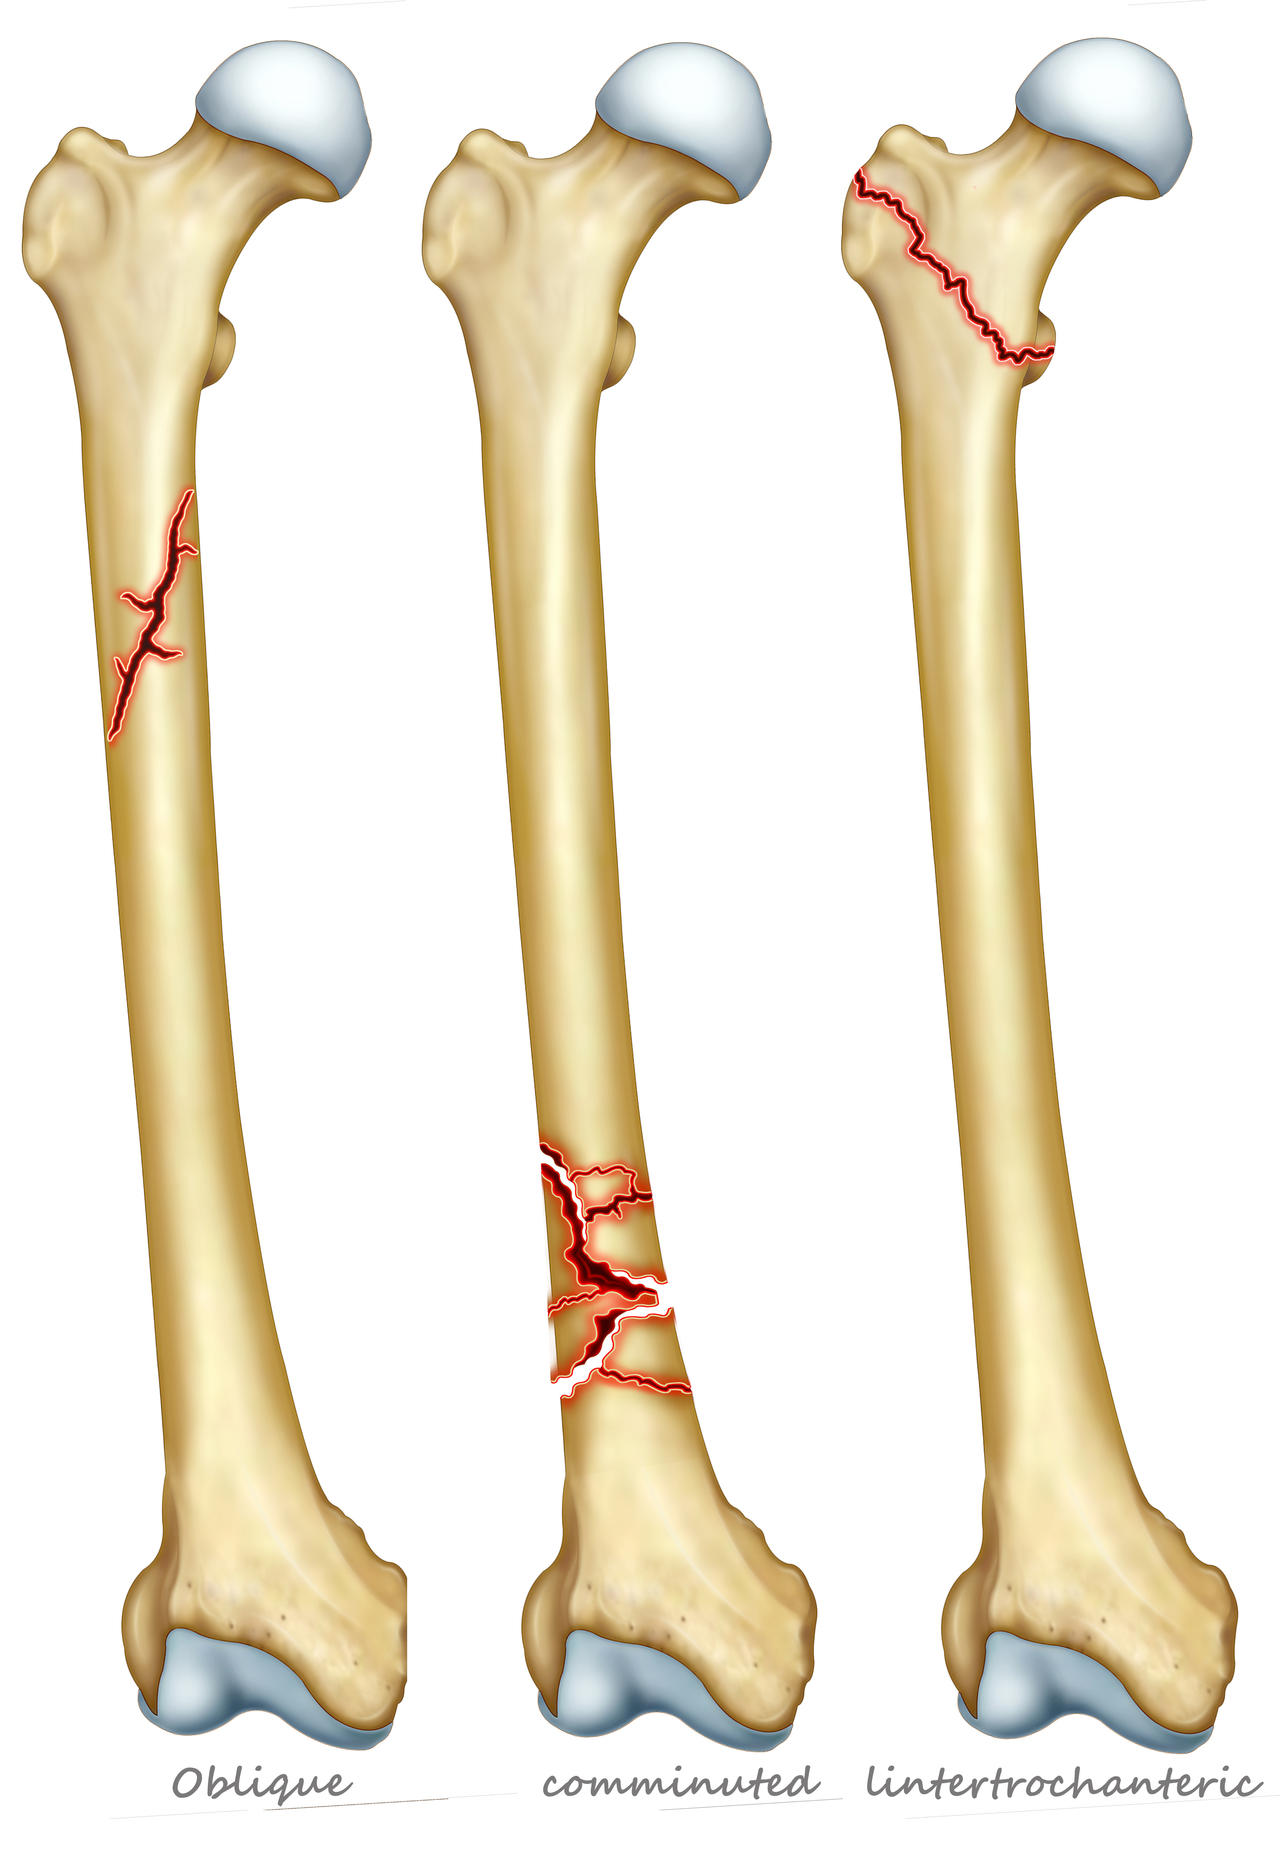

L’osteoporosi può diventare severa quando sono già presenti una o più fratture da fragilità ossea.

Le sue conseguenze sono una diminuzione della densità minerale ossea e un aumento della fragilità e debolezza dell’apparato scheletrico con predisposizione alla comparsa di fratture al collo del femore, al femore, ai corpi vertebrali, all’avambraccio e alla parte prossimale vicino alla spalla per quanto concerne la frattura dell’omero.

Queste fratture spesso richiedono un intervento chirurgico per la loro riparazione.

Le fratture possono anche accadere per movimenti del tutto normali, facenti parte della quotidianità, senza l’intervento di un trauma.

Spesso chi ha avuto fratture al femore presenta fratture vertebrali senza saperlo. I Pazienti che hanno subito una frattura al collo del femore, presentano in oltre il 50% dei casi, anche delle fratture vertebrali.

Una frattura al femore può anche ridurre il soggetto colpito in condizioni di disabilità fisica nel 20% – 30% dei casi.

I dati dimostrano che una bassa densità minerale ossea unita a una frattura possano aumentare notevolmente il rischio di subire ulteriori fratture:

- il 63% delle donne che hanno contratto una frattura femorale hanno già avuto fratture vertebrali;

- Chi ha registrato una prima frattura vertebrale da fragilità, ha un rischio di subire una frattura al collo del femore del 200%!

Attenzione: perché il femore può subire ulteriori fratture dopo la prima: nei successivi 5 anni dalla prima frattura le probabilità di subirne una nuova salgono al 20%. E le possibilità che venga colpito da frattura il femore della gamba opposta salgono al 50%. Spesso la frattura al femore può richiedere una lunga degenza.

Il femore è l’osso più lungo e resistente dello scheletro. È situato fra l’anca e il ginocchio e vi si inseriscono molti muscoli fondamentali per il movimento della gamba.

La sua resistenza può però ridursi con l’invecchiamento e può fratturarsi a livello del collo per minimi traumi o anche in loro assenza.